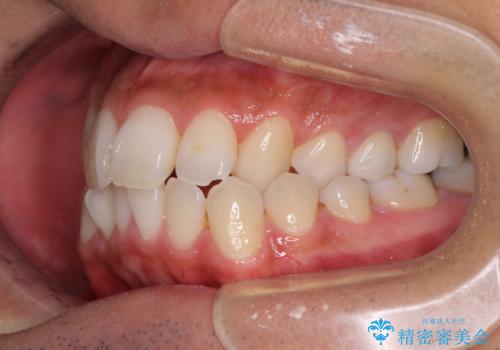

- 前歯のデコボコとクロスバイトを気にして来院された患者様です。

下顎の歯列弓に対して上顎歯列弓がやや小さく、側方の歯を中心にクロスバイトが見受けられました。

後方に隠れていた上顎前歯は矮小歯であるため、矯正治療の途中でオールセラミッククラウンを装着し、左右対称の大きさでの仕上がりを目指すこととしました。

奥歯の咬み合わせは接触が少なく物足りないように見えますが、患者様としては十分に咬むことができるとのことでした。